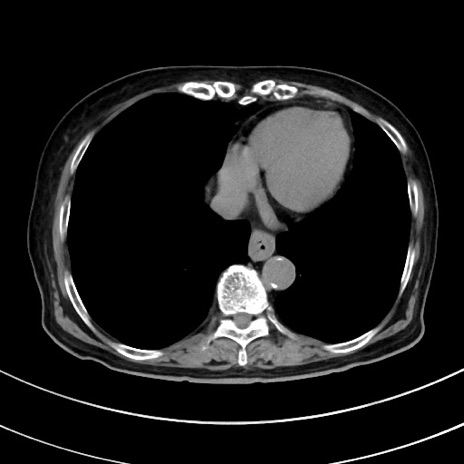

症例33(横断像)

【症例】70歳代 女性

【主訴】心窩部痛

【現病歴】延髄病変の精査・加療にて神経内科入院中。本日より心窩部痛あり。

【身体所見】右下腹部を中心に圧痛と反跳痛あり。